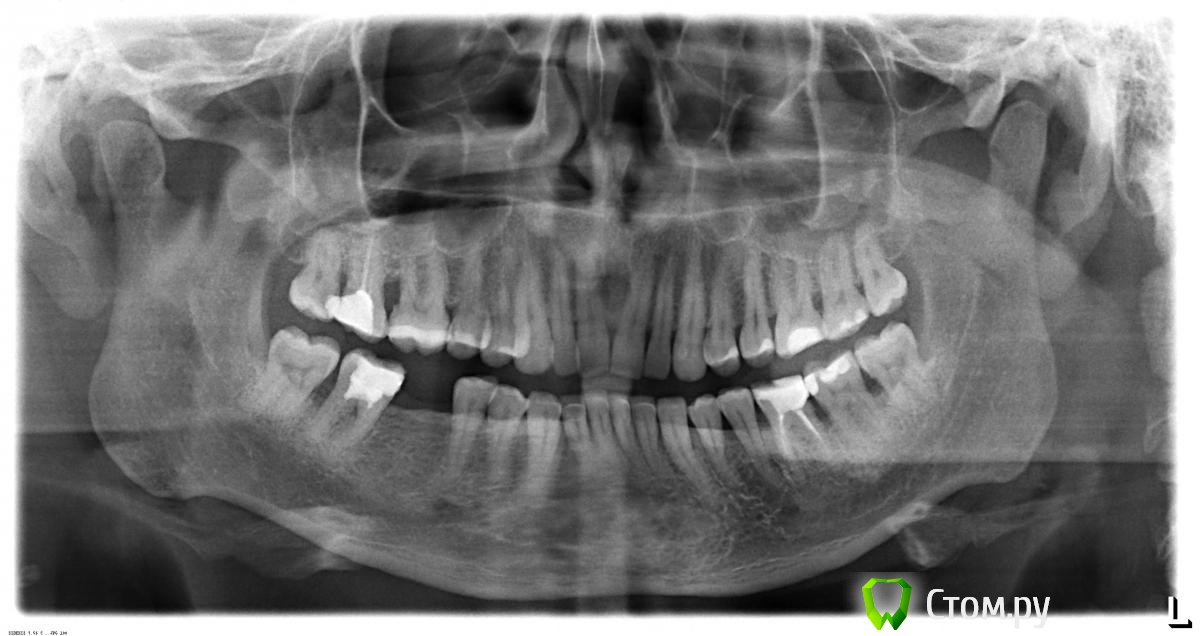

Reef Опубликовано 24 ноября, 2014 Поделиться Опубликовано 24 ноября, 2014 Посетил пару клиник, удивился отсутствием единого вектра лечения. Уважаемые профессионалы выскажите Ваше мнение, чтобы Я смог представить общую картину. 1. Мнение врачей первой клиники:1) парадонтоз, необходимо делать:- кюретаж отурытый в области 16 зубов;- ультразвуковую обработку тканей парадонта в области 20 зубов- установка лечебных пластин и Диплен-дента в области 8 зубов- антисептическая обработка патологических десневых карманов, склерозирующая терапия (1 процедура) - 1 фрагмент, 8шт.2) установка импланта в области 46 зуба 2. Мнение врачей второй клиники:1) неправильный прикус, необходимо исправление прикуса с помощью брекетов2) перестановка 47 и 48 зубов с помощью брекетов вперед, на место 46 и 47 сообветственно. ОРТО снимок прикрепляю. Ссылка на комментарий

red_butler Опубликовано 24 ноября, 2014 Поделиться Опубликовано 24 ноября, 2014 если судить только по ОПГ1. Профессиональная гигиена 2. консультация ортодонта3. повторное лечение корневых каналов в зубах 1.7 3.6 4.74. кюретаж пародонтальных карманов в области 1.6 1.7 3.6 3.7 4.7 4.85. Протезирование 1.7 3.6 4.7 6. имплантация 4.6 2 Ссылка на комментарий

Lolopop Опубликовано 24 ноября, 2014 Поделиться Опубликовано 24 ноября, 2014 округлое просветление на опг - артефакт съемки??? Ссылка на комментарий

red_butler Опубликовано 25 ноября, 2014 Поделиться Опубликовано 25 ноября, 2014 округлое просветление на опг - артефакт съемки??? в какой области? между 1.1/2.1? Ссылка на комментарий